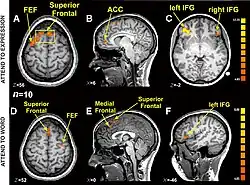

Cognitive and affective "paths": brain imaging data

Different brain structures involved in the recognition of a word, and in the recognition of an emotional expression (functional MRI).[48]

Research using functional magnetic resonance imaging of the brain suggests that cognitive and affective-expressive forms of communication and self-reflection have distinct neural bases.[50] Clinical findings have long suggested that verbalizations are often very incoherent when the individual is trying to put into words something deeply emotional.[51] Identification of words naming emotions (happy, neutral, sad) was found to be faster than identification of corresponding facial expressions. Recognition of face expressions was more difficult to suppress in favor of the recognition of words than vice versa, the two conditions presenting different patterns of brain activation. These experimental results suggest that reading and recognition of face expressions are stimulus-dependent and perhaps hierarchical behaviors, hence recruiting distinct regions of the medial prefrontal cortex.[48]

Research indicates that the representations of faces and objects in ventral temporal cortex are widely distributed and overlapping, face stimuli eliciting response patterns distinct from those elicited by object stimuli.[49]